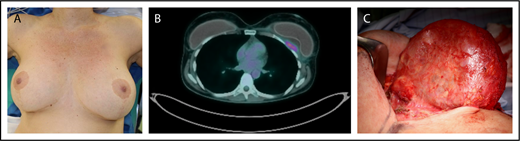

Clinical example of BIA-ALCL. Patient is a 42-year-old woman who presented with a late periprosthetic seroma of the left breast capsule (A) ∼7 years following cosmetic augmentation-mastopexy with bilateral textured breast implants. A fine needle aspirate (FNA) of the periprosthetic effusion demonstrated clonal expansion of CD30+ large anaplastic T cells. (B) A preoperative PET/CT scan demonstrated a posterior capsule wall mass invading the chest wall. (C) Specimen from a bilateral explantation; total capsulectomy with excision of the skin involvement demonstrated a posterior mass on the capsule. Complete surgical excision is essential as residual disease is associated with disease progression.